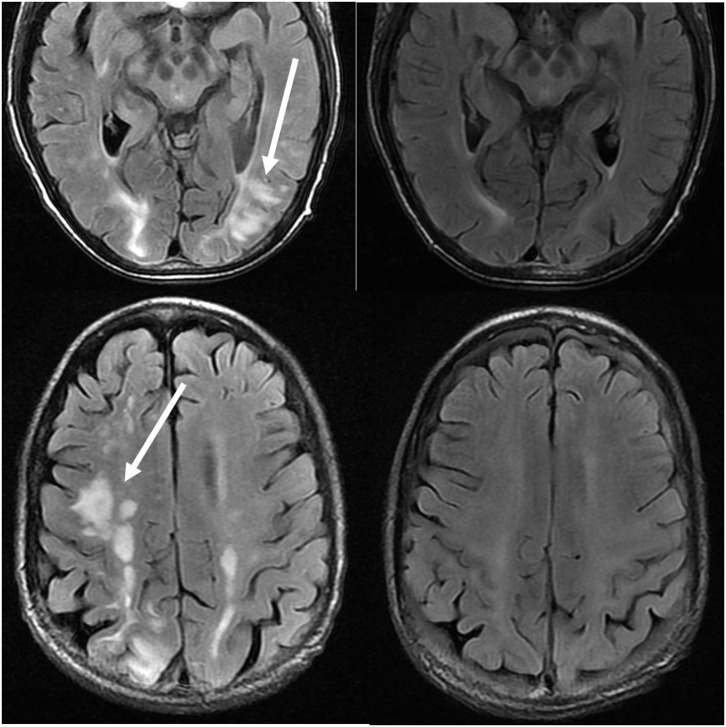

Figure 4.

Patient with systemic lupus erythematosus and rapidly progressive glomerulonephritis presenting with seizure. T2-FLAIR images of the head demonstrates vasogenic edema in the bilateral parietal and occipital lobes, left greater than right, as well as extension into the left frontal lobe. Note that with the vasogenic pattern of edema, there is sparing of signal abnormality in the cortex.